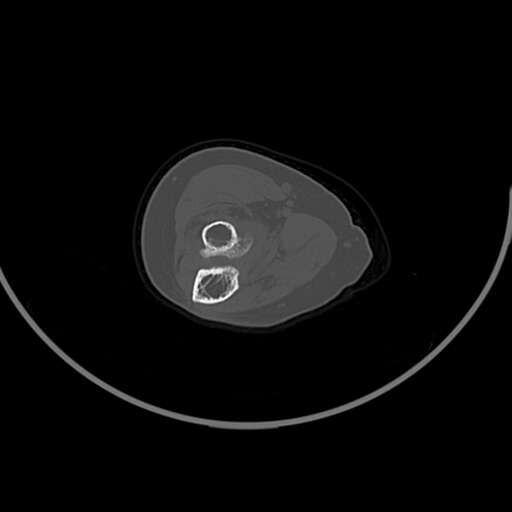

左肘部肿物

图2

女83岁,